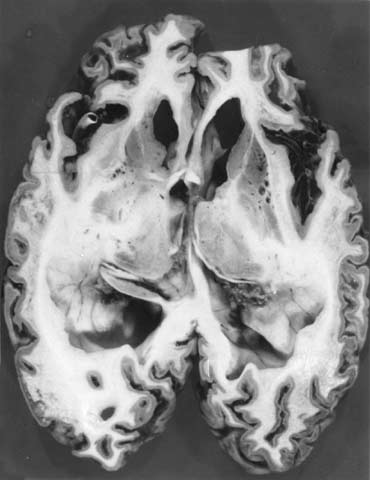

解剖脳の病理検索では皮質の萎縮、特有の海綿状変化、神経細胞の脱落、アミロイド斑などが指標となる。異常プリオン蛋白からなるアミロイド斑を抗プリオンペプチド抗体によって免疫染色した例(北大分子細胞病理、長嶋和郎教授供与)を示す(写真2)。小脳顆粒層の境界部に抗体によって染色された部分を認める。PCRによるゲノムの解析では、血液などから抽出したゲノムDNAをもとにプリオン遺伝子のシークエンスを決定する。日本人の遺伝性プリオン病では、東北大の北本哲之教授らによってコドン102、105、145、178、180、198、200、210、217、232などに変異が発見されている。